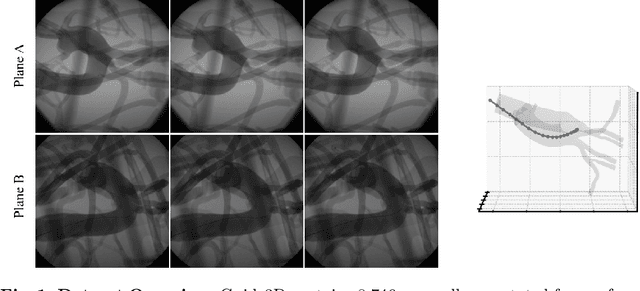

Abstract:Endovascular surgical tool reconstruction represents an important factor in advancing endovascular tool navigation, which is an important step in endovascular surgery. However, the lack of publicly available datasets significantly restricts the development and validation of novel machine learning approaches. Moreover, due to the need for specialized equipment such as biplanar scanners, most of the previous research employs monoplanar fluoroscopic technologies, hence only capturing the data from a single view and significantly limiting the reconstruction accuracy. To bridge this gap, we introduce Guide3D, a bi-planar X-ray dataset for 3D reconstruction. The dataset represents a collection of high resolution bi-planar, manually annotated fluoroscopic videos, captured in real-world settings. Validating our dataset within a simulated environment reflective of clinical settings confirms its applicability for real-world applications. Furthermore, we propose a new benchmark for guidewrite shape prediction, serving as a strong baseline for future work. Guide3D not only addresses an essential need by offering a platform for advancing segmentation and 3D reconstruction techniques but also aids the development of more accurate and efficient endovascular surgery interventions. Our project is available at https://airvlab.github.io/guide3d/.